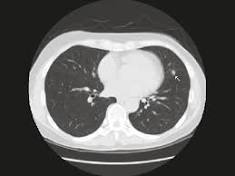

Although clinical trials have shown that lung cancer screening using low-dose computed tomography (LDCT) can detect lung cancers early and ...

Younger patients – aged 50 to 64 – are more likely to be diagnosed with late stage lung cancer than older patients according to new data* being ...